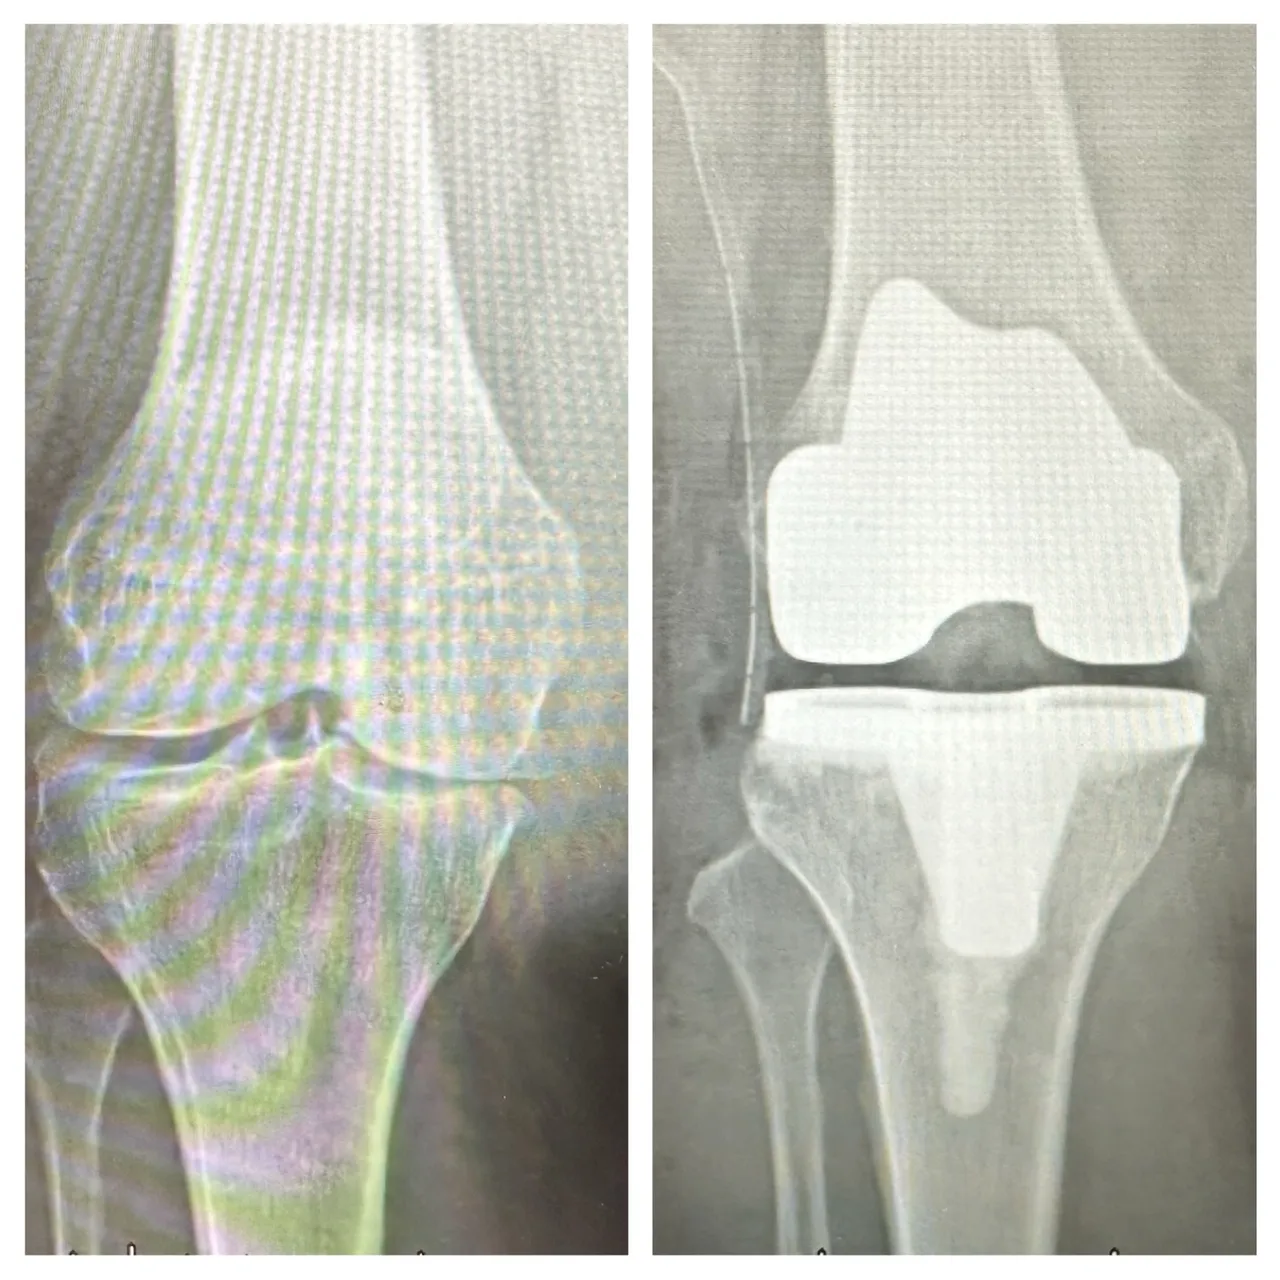

梁奶奶順利完成膝關節「人工關節置換手術」,術後疼痛明顯改善,短時間內即可重新站立並行走。豐原醫院提供